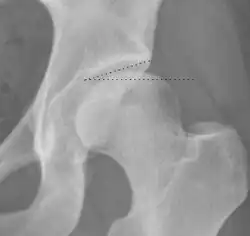

Projectional radiography ("X-ray") is often considered first line for FAI.[10] Anterior-posterior pelvis and a lateral image of the hip in question should be attained.[10] A 45-degree Dunn view is also recommended.[10][19]

| Alpha angle | ![]() |

Degree of bulging of the femoral head-neck junction: In normal conditions there is a symmetric concave contour at the junction of the femoral head and neck. Loss of this concavity or bone bulging may lead to cam type impingement. The degree of this deformity can be measured by the alpha angle. Although it can be measured in the cross-lateral view, the 45° Dunn view is considered more sensitive and the frog leg view more specific in determining pathologic values. |

|

| Femoral head-neck offset | ![]() |

Offset of the femoral head with regard to most prominent aspect of the femora neck | >10 mm |